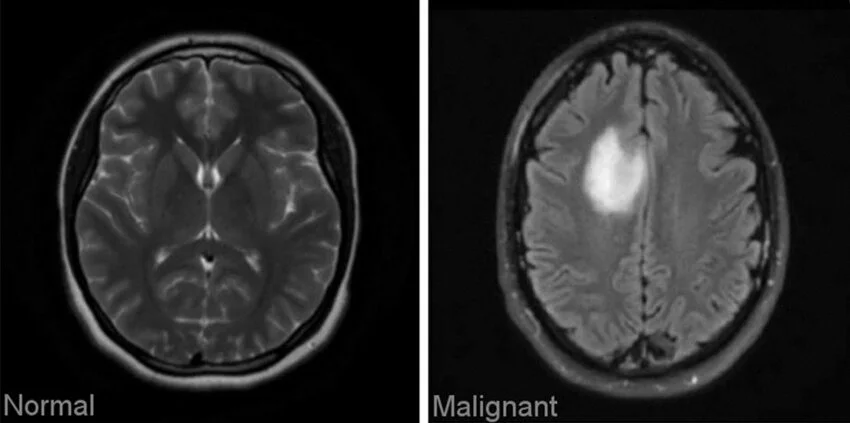

Sample Images from a Dataset of Brain Tumors (Source)

A recent example comes from researchers at Harvard Medical School, who trained an AI system using annotated digital pathology slides from multiple cancer types. The model learned to detect cancer cells, predict a tumor’s molecular profile, and estimate patient survival by analyzing visible cellular features.

It also identified patterns in the tissue surrounding tumors that relate to how patients respond to treatment. This level of performance was made possible through precise and consistent tumor annotation.